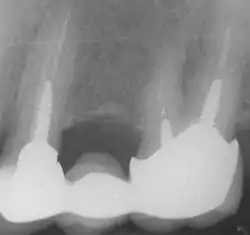

In the picture at right, the two teeth on the extreme left and right are the ones under discussion. The two teeth in the middle have been endodontically treated, but do not have post and cores.